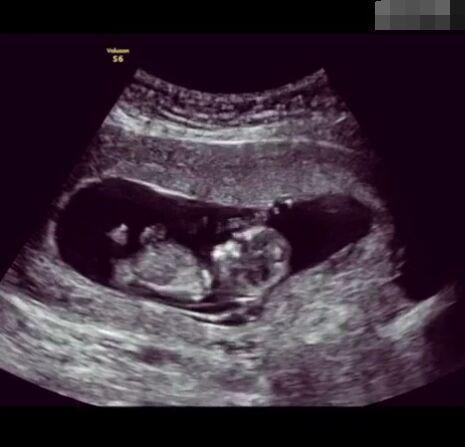

那些做了B超檢查確定胎兒男女,生下來后發(fā)現(xiàn)不對的,多半是因?yàn)樵贐超檢查時(shí)寶寶太調(diào)皮,以致影響了檢查準(zhǔn)確性。就比如說,有的女寶寶在媽媽肚子里玩自己的臍帶,把臍帶夾到了兩腿中間,B超就有一定幾率拍出來好像是男寶寶的特征,導(dǎo)致被誤認(rèn)為是男孩子。還有些男寶寶過分害羞,在做B超時(shí)雙腿緊緊并攏,醫(yī)生也很難判斷男女,只好大致猜測是女孩,就又造成了誤會。因此,B超亦不是萬能的。